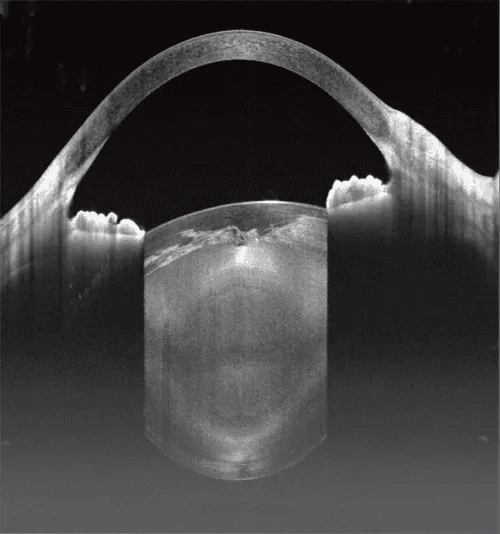

Swept-source OCT with full-range imaging capability, offering 12mm posterior scan depth and 15mm anterior scan depth with sub-6 micron optical resolution, utilizing 1060nm wavelength technology for improved penetration through cataracts and vitreous opacities

Anterior Segment:

Scan depth: 15mm

Maximum line scan length: 24mm

Full-range imaging without separate anterior/posterior switching

Enhanced imaging through cataracts and vitreous opacities

Single-device solution for comprehensive anterior and posterior segment imaging